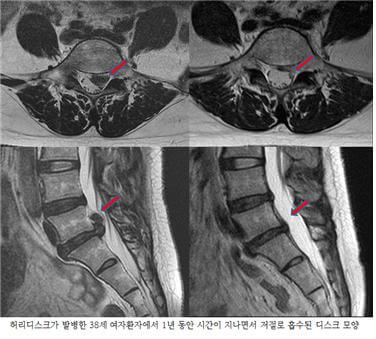

추간판 탈출증이라 불리는 허리디스크 증상은 크게 3단계로 나눌 수 있어요. 1단계는 내부 섬유륜이 파열하여 수핵이 빵빵한 상태, 2단계는 섬유륜 전체가 파열되어 수핵이 탈출하는 단계, 3단계는 완전히 탈출해 버린 단계입니다.

단계마다 느끼는 증상들이 조금씩 다른데요. 디스크의 보호막이 약간 찢어졌고 디스크가 약간 튀어 주변의 신경 뿌리에 닿으면 염증성의 통증이 발생하기 시작하면서 점점 증상이 심해지면 디스크의 파열은 골수를 이루고 있는 핵이 튀어나오면서 신경에 대한 물리적 압박을 가하고 참을 수 없는 아픔을 유발하게 돼요.